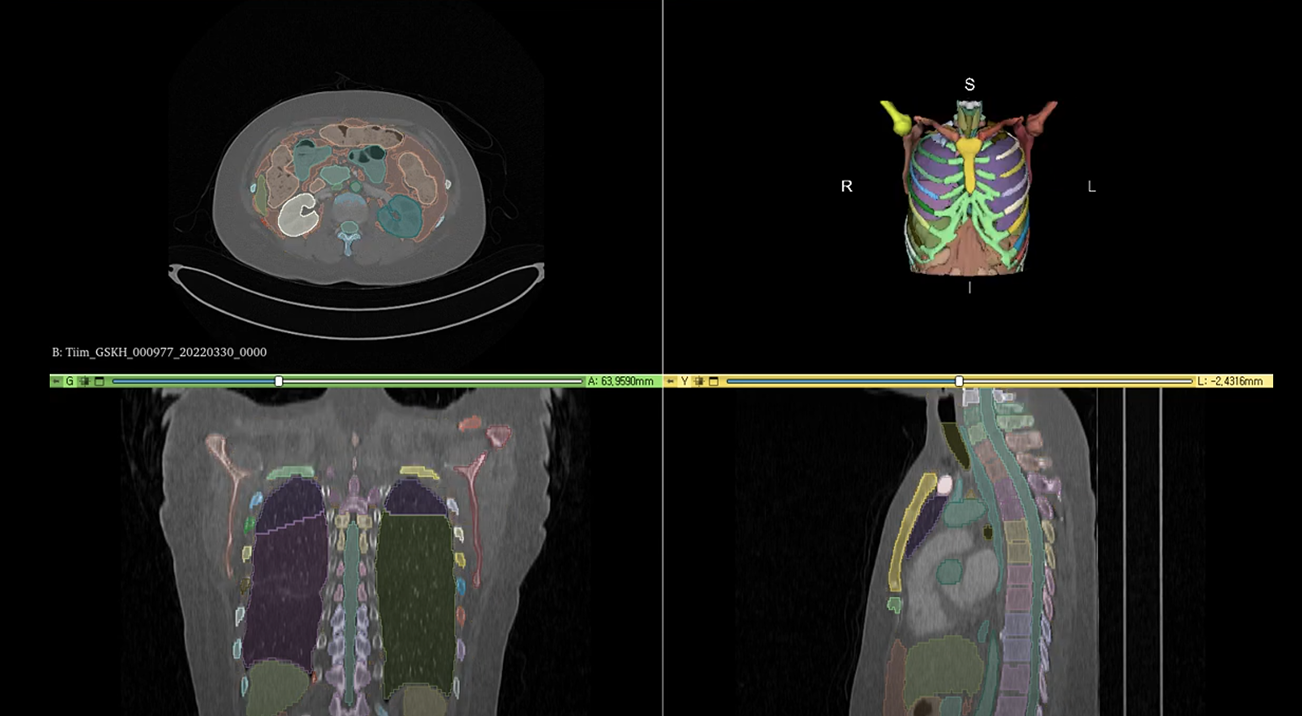

- 진단 자동화 지원 (RECIST & Segmentation)

폐암 진단 추적을 위한 RECIST 가이드라인 자동화 및 3D 디지털 트윈 솔루션과 연동하여, 의료진에게 데이터 기반의 직관적인 리포트를 제공합니다. - 의료 논문 키워드 자동 추출 및 분석